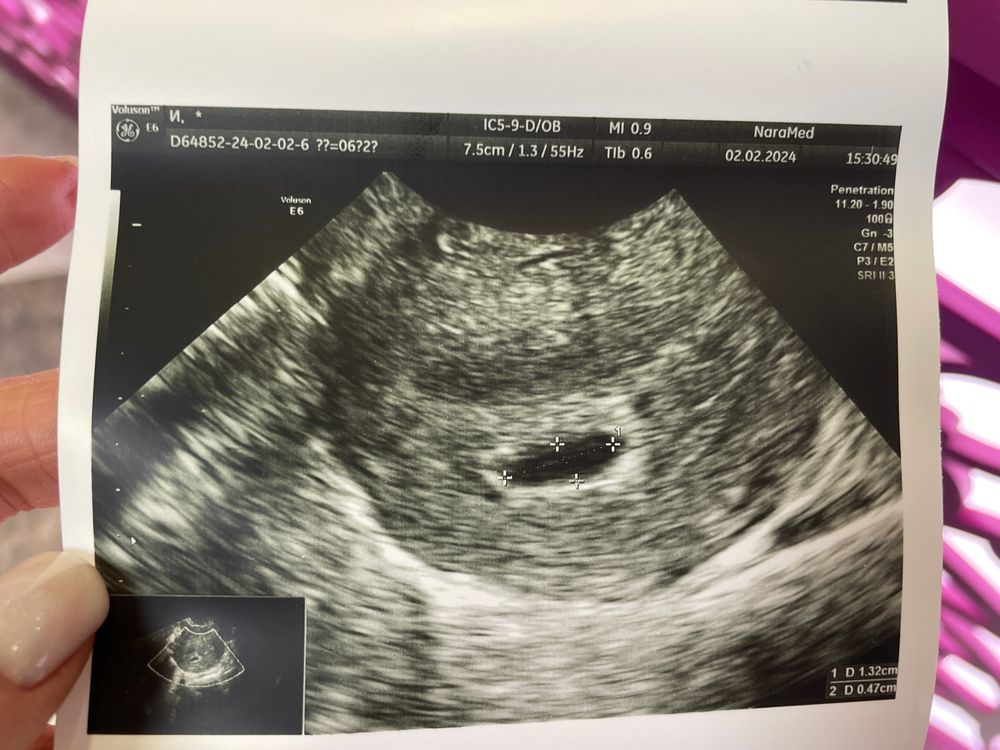

Первая беременность, не видно эмбрион

Ждите до 20 мм Диагноз анэмбрионии (пустое плодное яйцо) предполагается, если в плодном яйце размером 20 мм не определяется желточный мешок. Или если плодное яйцо диаметром более 25 мм с желточным мешком не содержит эмбриона. А также при размере желточного мешка 10 мм и более

Тетя Кошка, спасибо большое, ждем… тем более оно сейчас еще и неправильной формы… по одной стороне 13, по второй всего 5… Ждем и верим 🙏🏻🙏🏻🙏🏻

Марина, ну вот сегодня не увидели ничего 😔😔😔 только овальной формы яйцо и всё…